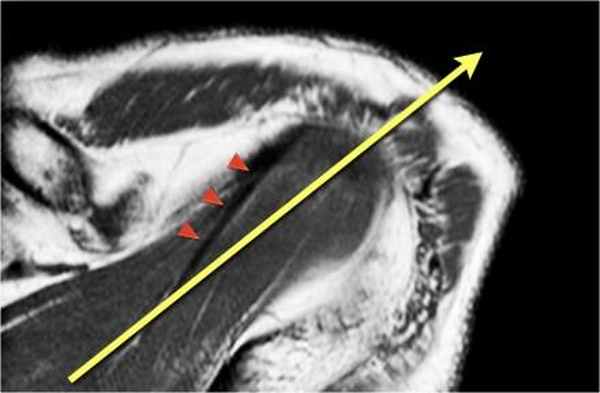

Ось сухожилия надостной мышцы

Подвергаясь тендинопатие и повреждению, сухожилие надостной мышцы является важнейшей частью манжеты вращателей. Повреждения сухожилия надостной мышцы лучше видны в косой корональной плоскости и в положении отведения и поворота плеча кнаружи (ABER - abduction external rotation). В большинстве случаев ось сухожилия надостной мышцы (головки стрелок) отклонена кпереди от оси мышцы (желтая стрелка). При планировании косой корональной проекции лучше ориентироватьия на ось сухожилия надостной мышцы.